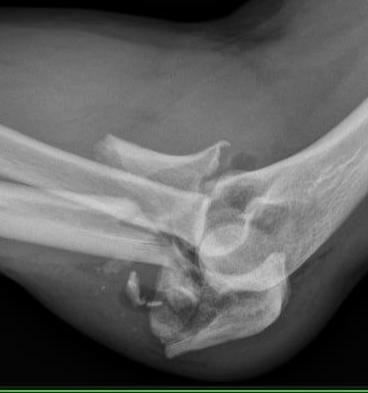

Proximal ulna fracture dislocations

- proximal ulna fracture +

- spectrum of other injuries including radial head and coronoid fractures

Simple Monteggia fracture - proximal ulna fracture with posterior radial head dislocation without fracture

Monteggia variant / Complex Monteggia fracture dislocation

- Monteggia fracture + posterior radial head fracture +/- coronoid fracture

Proximal ulna / olecranon fracture

- posterior radial head dislocation most common in adults

- no fractures

Elbow dislocation + olecranon fracture + radial head/neck fracture +/- coronoid fracture